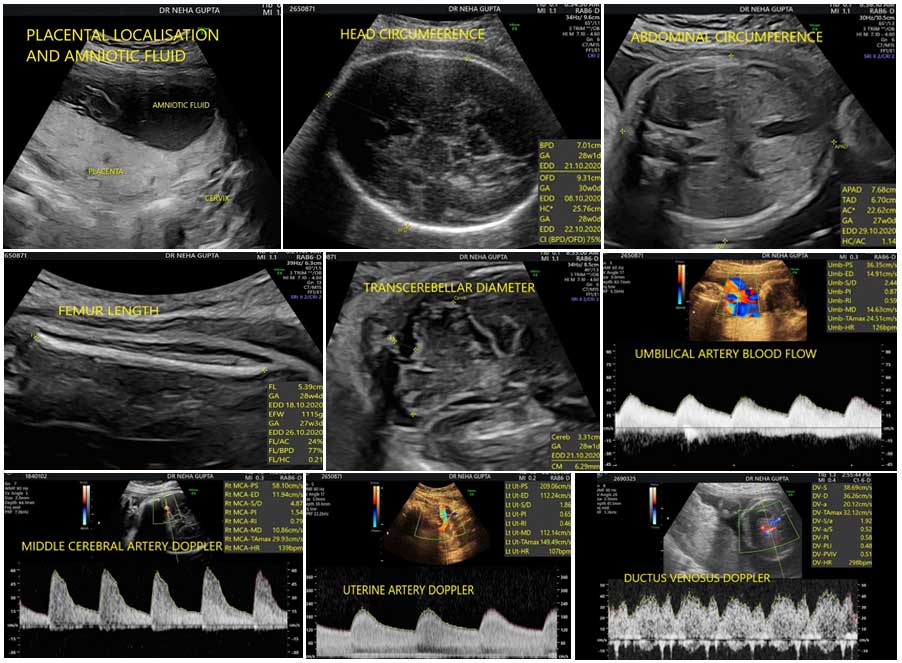

This scan is meant to assess the fetal weight, the fluid around the baby, the placental localisation and the blood flows to the baby.

Fetal dopplers mean assessment of baby’s blood flows. Maternal blood flows to the uterus are assessed by uterine artery Dopplers. Blood flow through cord is called as umbilical artery blood flow. Blood through baby’s brain is called as middle cerebral artery Dopplers and through tummy is referred to as ductus venosus Dopplers.

The aim is to assess the fetal growth disorders and the well being of the unborn baby. If the growth is appropriate for the weeks, then it is normal. If the growth is small, then it is a weak baby, also called as fetal growth restriction. If the growth is high, then it is a big baby, also called as macrosomia.

Besides fetal weight, maternal history and symptoms, fluid assessment and baby’s blood flows helps us to further identify the babies at risk of adverse outcome. Depending on the above factors, appropriately delivery can be timed.